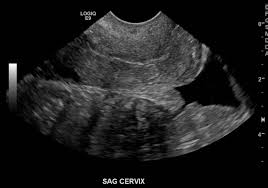

Okay, let’s break down the cul-de-sac in ultrasounds. It’s a term you’ll hear if you’re having a pelvic ultrasound. It’s basically a pouch, or a little pocket, in the pelvic cavity.

You see, women have two of these cul-de-sacs. One’s in the front of the uterus, between the uterus and the bladder. This is called the anterior cul-de-sac. The other cul-de-sac is behind the uterus, between the uterus and the rectum (your bottom). This one is called the posterior cul-de-sac.

The cul-de-sac is a common finding in ultrasounds. Your doctor will likely mention it, especially if they see fluid there. Don’t worry – it doesn’t necessarily mean anything is wrong. But it’s important to know what it is and why your doctor might be looking at it.

Sometimes, fluid can build up in the cul-de-sac, a pouch-like area behind the uterus. This fluid is often collected for testing with a fine needle inserted through the wall of the vagina. This process is called culdocentesis.

The fluid is examined under a microscope to look for infection or other abnormalities. If the test reveals an infection, your healthcare provider will likely prescribe antibiotics.